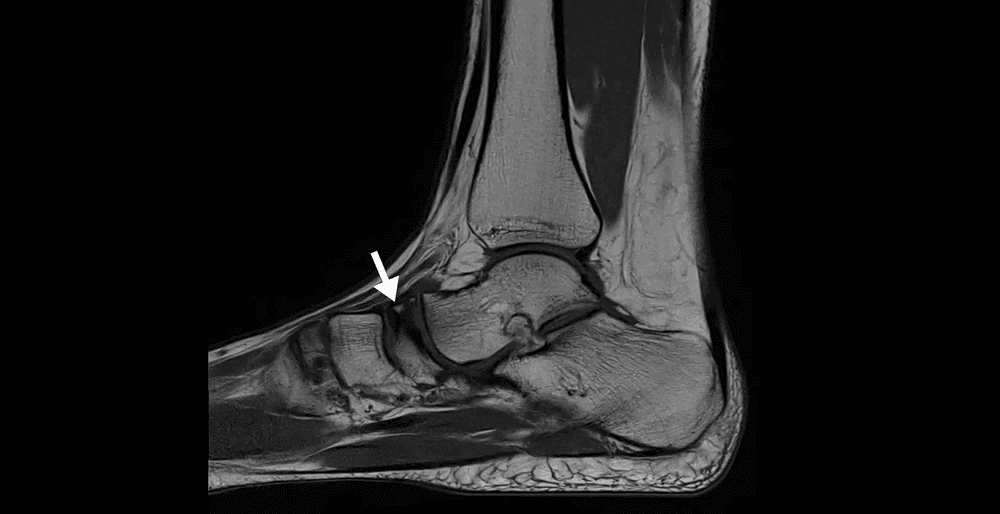

Cas d'une maladie de Köhler, ostéochondrose rare de l'os naviculaire du pied.

MRI

Douleur aiguë de l'arrière-pied chez un patient de 70 ans lors d'un changement de direction brutale pendant la marche.